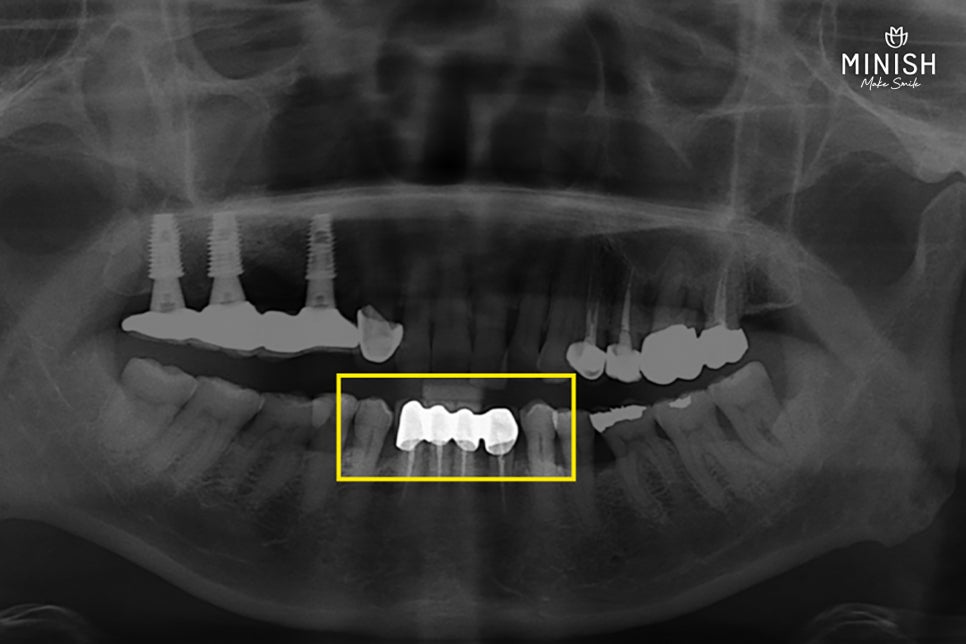

보철을 위해 건강한 치아 표면을 과하게 삭제한 탓에, 결국 신경까지 건드리는 과정이 불가피해졌습니다.

▷ 왜 과도한 삭제가 이뤄졌을까요?

크라운은 치아 전체를 덮는 구조로 제작되며, 재료의 특성상 일정한 두께를 확보해야만 깨지거나 부러지지 않고 강도를 유지할 수 있습니다. 하지만 이 두께를 확보하기 위해 치아를 깎지 않고 그대로 덮는다면, 치아가 뚱뚱하게 부풀어 보이거나 주변 치아와 조화롭지 않게 보일 수 있습니다. 결국 공간을 확보하기 위해, 건강한 치아 표면까지 비교적 넓게 삭제하는 과정이 이뤄지게 됩니다.

▷ 신경을 건드리는 처치, 왜 조심해야 할까요?

신경을 다룬다고 해서 상처를 회복시키는 과정은 아닙니다. 오히려, 치아 내부의 신경(치수)을 완전히 제거해 세균 침투를 차단하는 방식입니다. 이 과정에서 감각을 느끼는 신경도 함께 사라지기 때문에, 이상이 생겨도 통증이 없어 알아차리기 어려운 상태가 됩니다.

또한, 신경이 제거된 치아는 내부가 비어 있어 수분이 공급되지 않고 점차 건조해지며 결국엔 푸석하게 마르면서 외부 자극에 약하고 쉽게 깨질 수 있는 구조로 바뀝니다.

신경을 다룬 이후 약해진 평택엄마의 치아는 크라운 재치료가 필요했습니다.